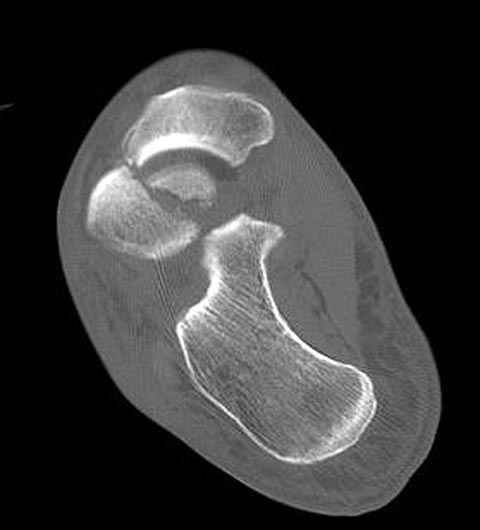

В декабре у меня был пациент с политравмой и аналогичным повреждением тарана с подвывихом в таранно- ладьевидном суставе, единственное отличие - отломок головки тарана был меньше по размеру и фрагментирован, поэтому его фиксация была невозможна.

Для доступа к задне-медиальному суставному фрагменту я выполнил косую остеотомию внутренней лодыжки у её основания -получается хороший доступ к голеностопу, адекватный обзор и возможность восстановить суставную поверхность. фрагмент фиксировал двумя 3,5 мм спонгиозными винтами с неполной резьбой, *утопив* головки винтов в кость. Аналогичная фиксация и двумя тягловыми винтами и внутренней лодыжки. \в качестве альтернативы для

фиксации фрагмента тарана можно было бы использовать и герберт винты, но по организационным причинам :-(( набора не оказалось под рукой).

Повторный осмотр назначил через 2 мес с момента операции. Отдаленных наблюдений такого подхода у меня нет( достаточно редкий тип повреждений таранаHawkins II), но наблюдения в ближайшем послеоперационном периоде выглядели вполне прилично, на мой взгляд.